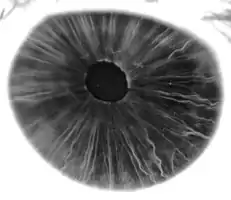

Iris, front view